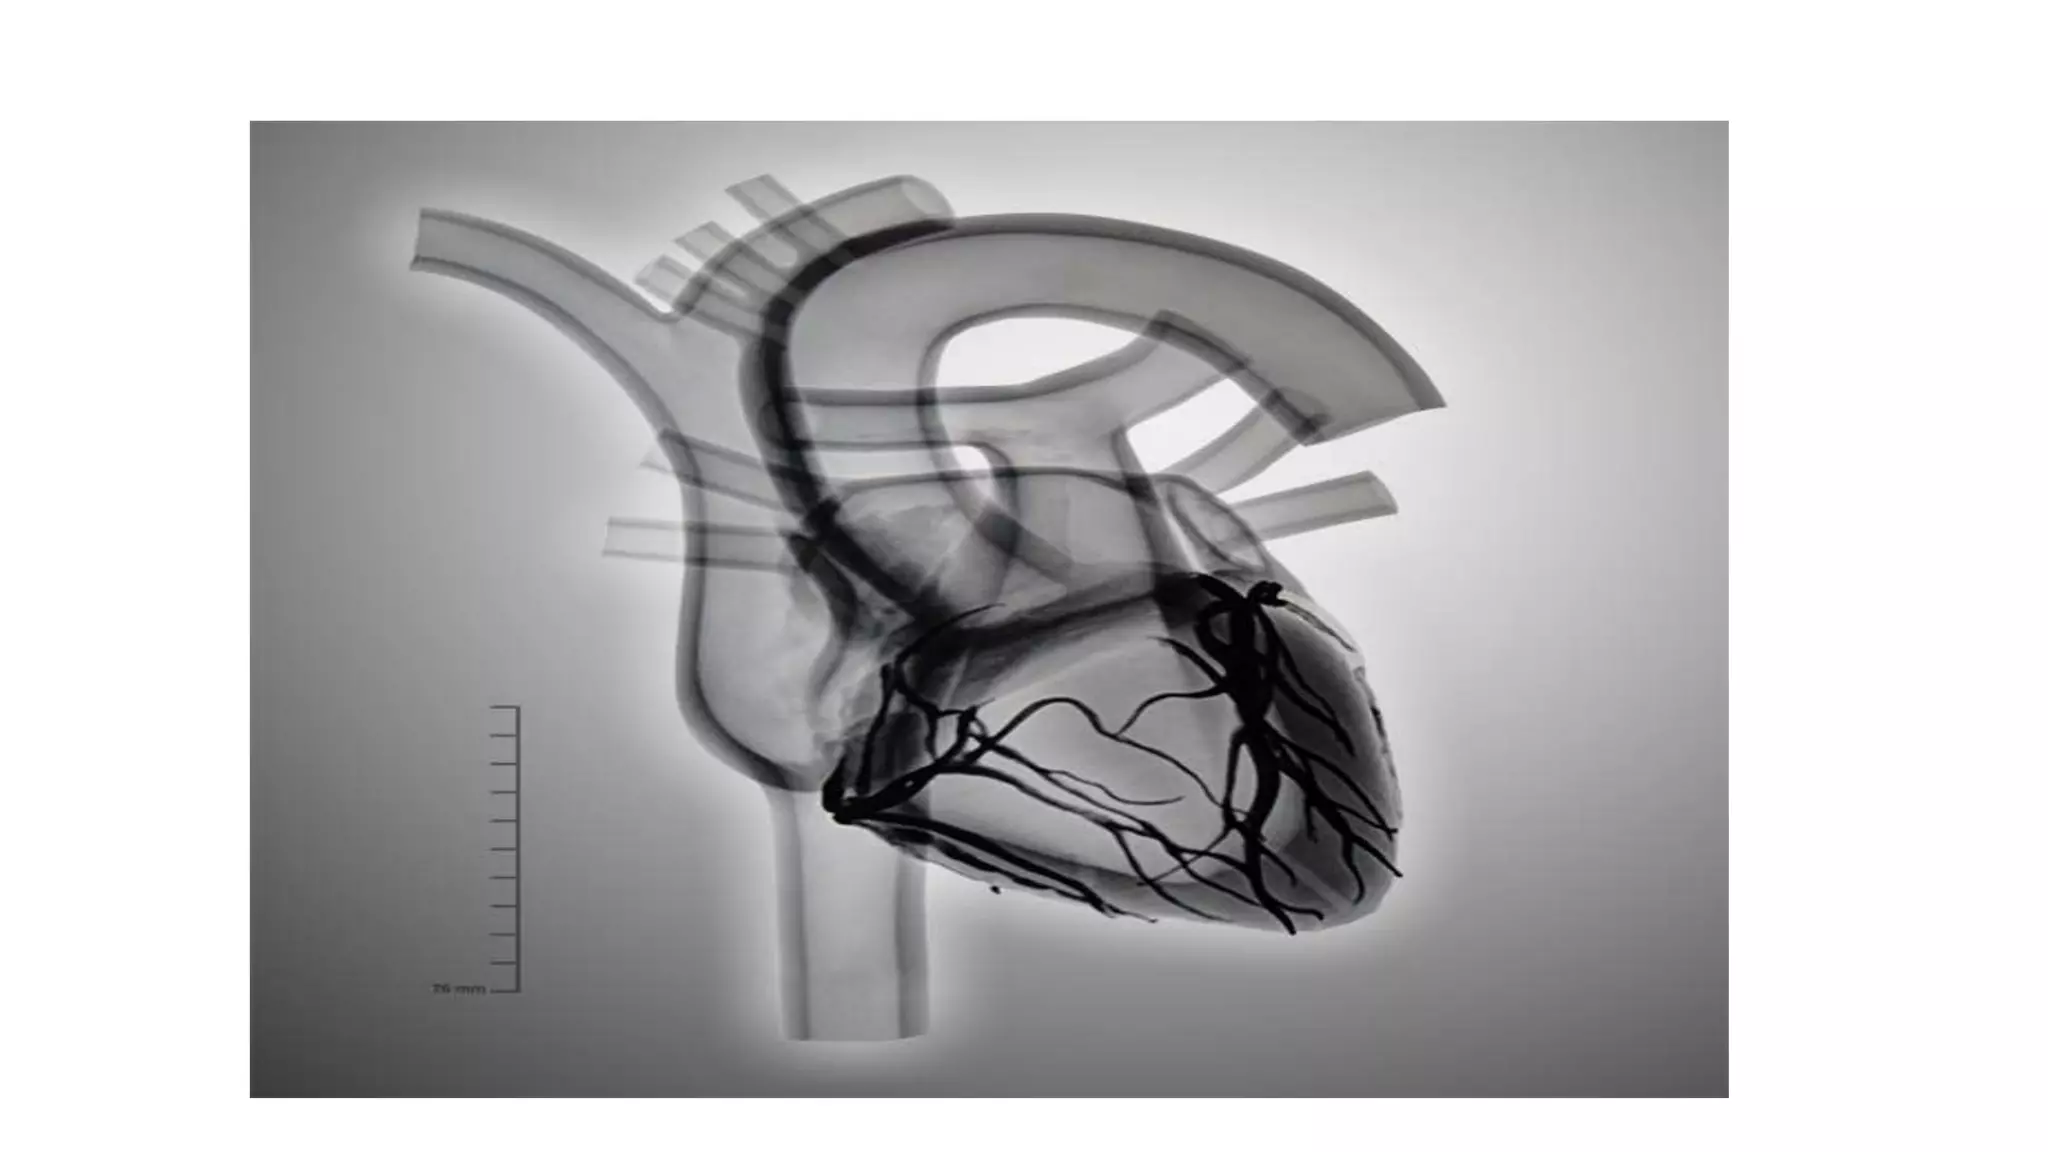

• Fluoroscopy isan x-ray imaging technique that allows visualization of the heart on a screen. • It shows cardiac and vascular pulsations and unusual cardiac contours. • During a fluoroscopy procedure, an X-ray beam is passed through the body. The image is transmitted to a monitor so the movement of a body part or of an instrument or contrast agent ("X-ray dye") through the body can be seen in detail.